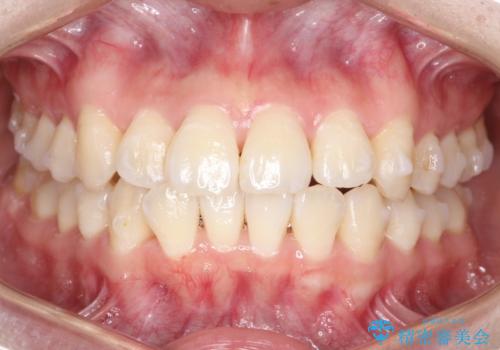

【インビザライン】前歯の凸凹をなおしたい

- 前歯の凸凹をなおしたいことを主訴にインビザラインにて矯正治療を行いました。

患者様にしっかりとインビザラインを使用して頂けたことで綺麗な仕上がりとなりました。